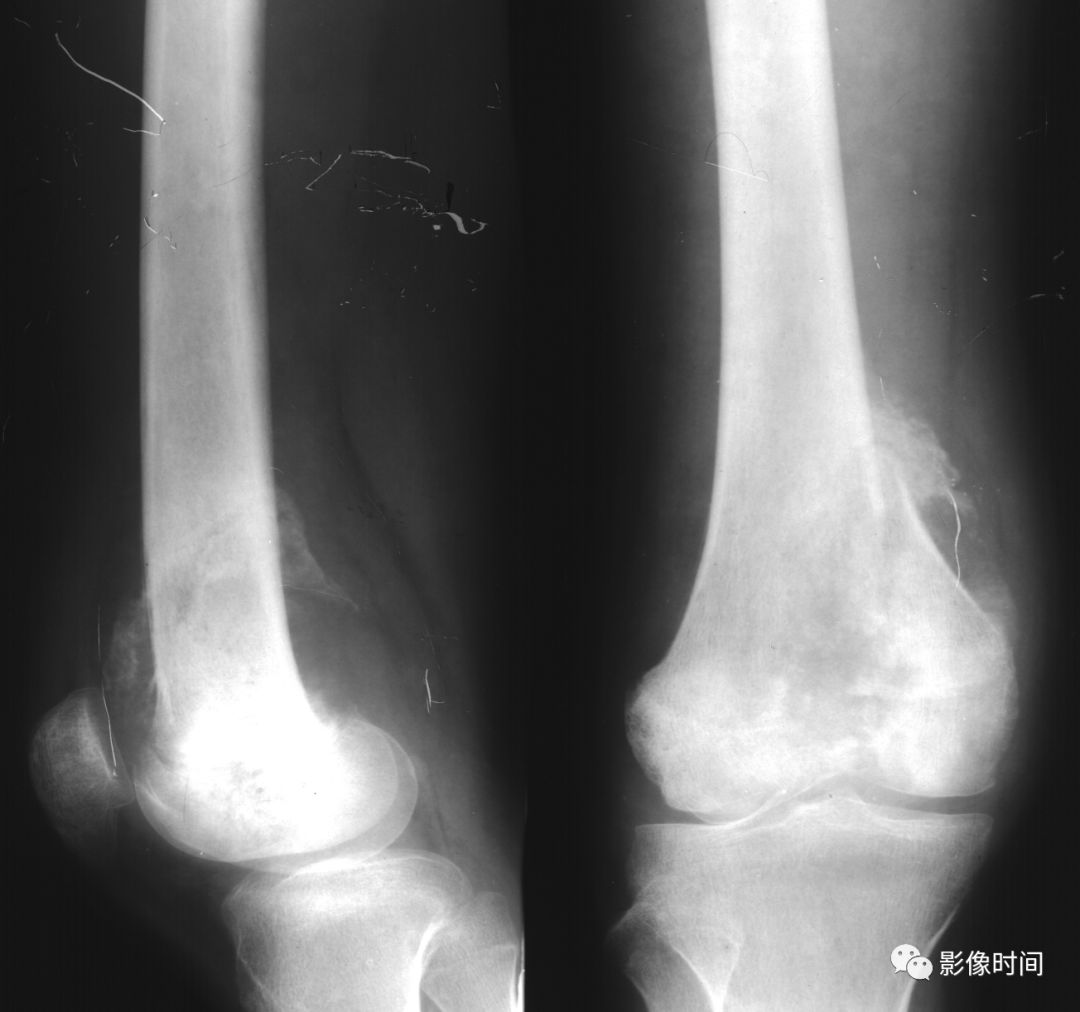

(四)压迫性骨质缺损   压迫性骨质缺损系因骨皮质局部受压,致使骨萎缩以致缺损、消失出现碟形的骨质缺损(图 12、图 13、图 14)。

多为邻近骨表面的软组织肿瘤或邻近骨肿瘤压迫或侵蚀骨质所致。

一般情况下,骨缺损的边缘都相当锐利且与正常骨质间有明显界限。

图 12  压迫性骨缺损:骨软骨瘤